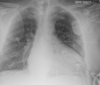

4

Q

A

Pericardial effusion